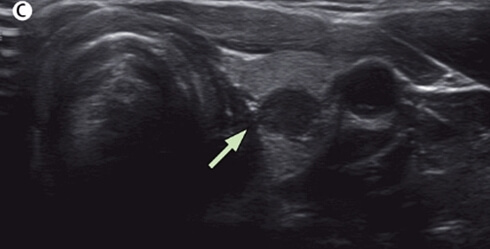

갑상선 유두암은 갑상선에 발생하는 몇 가지 암들 중에서 고주파 치료를 해볼 만한 암입니다. 갑상선 유두암 중에서도 크기가 1cm 이하인 유두암을 미세유두암이라고 부릅니다.

그리고 갑상선 미세유두암 중에서도 피막침범이 없고, 림프절 전이가 없으며, 타 장기로 원격 전이가 되지 않은 미세유두암을 저위험군 미세유두암이라고 부릅니다.

이러한 미세유두암부터가 고주파 절제술의 대상입니다. 최근에 나오는 갑상선 미세유두움 고주파 치료의 많은 연구 결과들을 보면 대게 저위험군 미세유두암 환자들을 대상으로 치료를 했습니다.